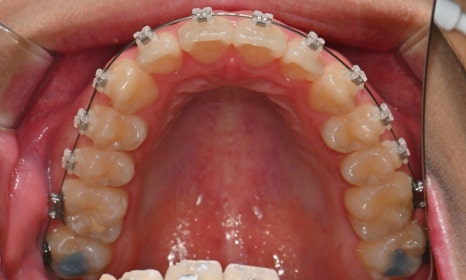

치료 시작 7개월 후 - 연세정원치과

치료 시작 7개월 후 사진으로, 치아 배열 후 아래 우측에 미니스크류를 식립하여 치아 중심선을 개선하는 중으로, 교합과 치아 중심선이 많이 개선된 것을 확인할 수 있습니다.